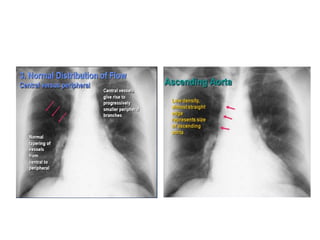

Pulmonary Vessels

1. Measure the right descending Pulmonary artery

Diameter- (16mm in Male & 15mm in Female)

2. Distribution of flow from apex to base

• At first intercostal space– normal vessels not more than 3

mm in diameter

• Erect- Lower lobe vessels prominent

• Supine- Equalize

3. Distribution of flow from central to peripheral -

tapering

• Vascular lung markings- Central 2/3rd

Pulmonary Vessels 1. Measurethe right descending Pulmonary artery Diameter- (16mm in Male & 15mm in Female) 2. Distribution of flow from apex to base • At first intercostal space– normal vessels not more than 3 mm in diameter • Erect- Lower lobe vessels prominent • Supine- Equalize 3. Distribution of flow from central to peripheral - tapering • Vascular lung markings- Central 2/3rd